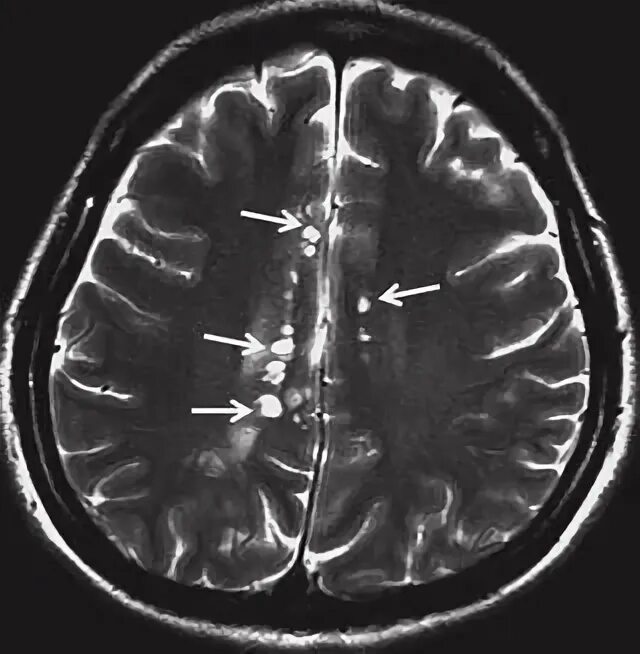

Периваскулярные пространства базальных ядер